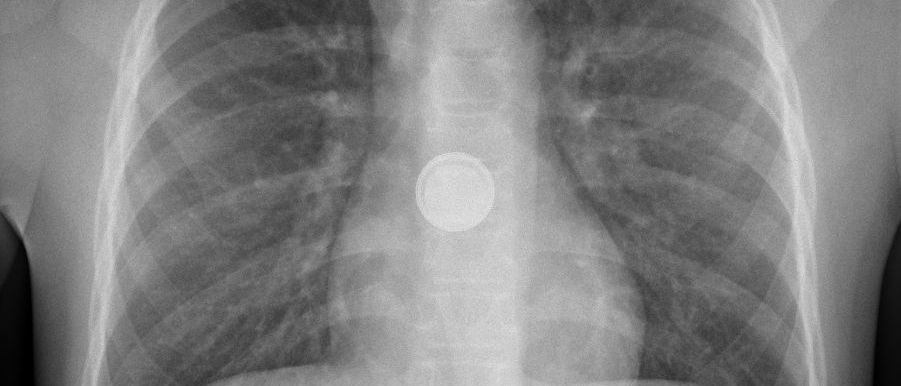

Baby Elias* ist zehn Monate alt, als er auf einmal nichts mehr essen will. Als seine Eltern bemerken, dass er generell nicht mehr schluckt, bringen sie ihn sofort ins Kinderspital auf den Notfall. Auf dem Röntgenbild wird ein Fremdkörper in Elias Speiseröhre ersichtlich. Es folgt eine Notoperation unter Vollnarkose. Entfernt wird eine Knopfbatterie. Wie sich später herausstellt, hat Elias diese irgendwie aus einer Fernbedienung entnehmen können.